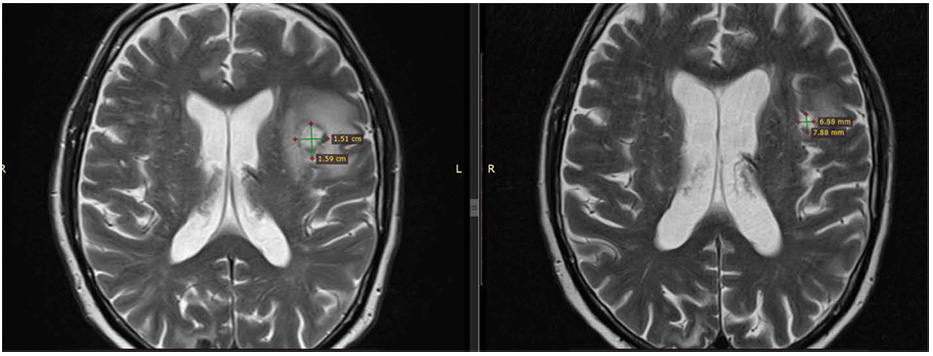

В декабре 2021 г. – лучевая терапия на весь объем головного мозга, суммарная очаговая доза 30 Гр, при контрольной магнитно-резонансной томографии (МРТ) головного мозга с внутривенным контрастом – появление новых очагов в головном мозге (суммарно до 11). С февраля по апрель 2022 г. проведено 3 курса терапии препаратом трастузумабом дерукстеканом, в динамике – частичный интракраниальный ответ (рис. 6, 7).

Рис. 6. Пациент №11, аксиальная проекция, сравнение МРТ головного мозга с контрастным усилением (КУ) от февраля 2022 г. (слева) и от апреля 2022 г. (справа), уменьшение целевого очага в левой теменной доле.

Fig. 6. Patient No.11, axial plane, comparison of contrast-enhanced brain MRI dated February 2022 (left) and April 2022 (right), reduction of the target lesion in the left parietal lobe.